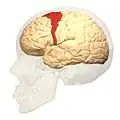

Brodmann area 6 (BA6) is part of the frontal cortex in the human brain. Situated just anterior to the primary motor cortex (BA4), it is composed of the premotor cortex and, medially, the supplementary motor area (SMA). This large area of the frontal cortex is believed to play a role in planning complex, coordinated movements.

Brodmann area 6 is also called agranular frontal area 6 in humans because it lacks an internal granular cortical layer (layer IV). It is a subdivision of the cytoarchitecturally defined precentral region of cerebral cortex. In the human brain, it is located on the portions of the precentral gyrus that are not occupied by Brodmann area 4; furthermore, BA6 extends onto the caudal portions of the superior frontal and middle frontal gyri. It extends from the cingulate sulcus on the medial aspect of the hemisphere to the lateral sulcus on the lateral aspect. It is bounded rostrally by the granular frontal region and caudally by the gigantopyramidal area 4 (Brodmann, 1909).[1]

Image

Medial view.

Medial view.